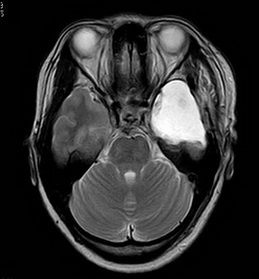

住院期间视频脑电图显示:重度异常脑电图;间期癫痫样发电,左侧颞区;先兆-肌张力障碍(右侧上肢)。头部MR提示:1.左侧海马萎缩、硬化;2.小脑轻度萎缩;3.右侧上颌窦粘膜下小囊肿。

术前MR